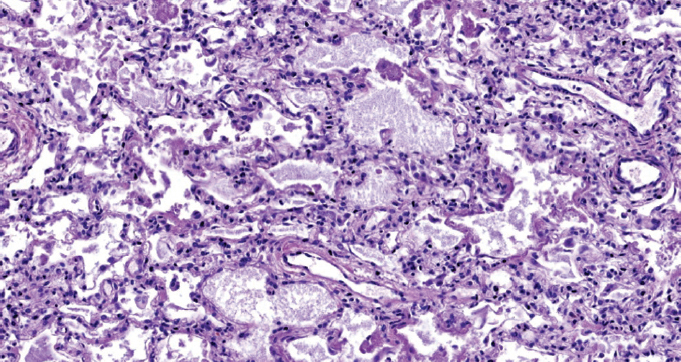

При патологоанатомическом исследовании — ткань легких с диффузными ателектазами, чередующимися с небольшими эмфизематозно расширенными участками, мелкоочаговыми кровоизлияниями в расширенные межальвеолярные перегородки (рис. 1). Большая часть альвеол звездчатой формы, очагово заполнены серозно-фибринозным экссудатом (рис. 2), слущенными альвеолоцитами, альвеолярными макрофагами (рис. 3). Часть альвеол выстлана гиалиновыми мембранами (рис. 4). Сосуды микроциркуляторного русла, расположенные в межальвеолярных перегородках, округлой формы, в просвете большей части которых определяются нити фибрина. Эндотелиальные клетки, выстилающие сосуды, набухшие, овальной формы, другие — более вытянутые, сохраненные не на всем протяжении стенки сосуда. Бронхи среднего и более крупного калибра звездчатой формы, стенка преимущественно утолщена за счет отека и склероза подслизистого слоя. Слизистая оболочка бронхов представлена цилиндрическим эпителием с дистрофическими изменениями, местами слущенным, в сохраненных участках с явлением пролиферации. В просвете бронхиол и более крупных бронхов выявляются десквамированный эпителий, единичные эритроциты, макрофаги. Кроме этого, преимущественно перибронхиально — диффузная лимфоцитарная инфильтрация с примесью умеренного количества нейтрофильных лейкоцитов; разрастание соединительной ткани, образование мелких единичных лимфоидных фолликулов.

Рис. 1. Чередование ателектазов с эмфизематозно измененными участками легкого. Окраска гематоксилином и эозином. Ув. ×100 / Fig. 1. Alternation of atelectasis with emphysematous altered areas of the lung. Stained with hematoxylin and eosin. Magnification ×100